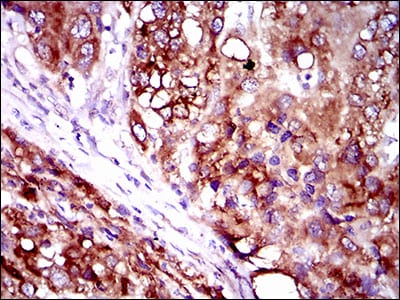

分类: 科研抗体货号: 30509别名: IRIS; PSCP; BRCAI; BRCC1; PNCA4; RNF53; BROVCA1; PPP1R53应用: IHC反应种属: Human

分类: 科研抗体货号: 30520别名: NMB; HGFIN应用: WB,IHC反应种属: Human

分类: 科研抗体货号: 30525别名: VLCS; FATP2; VLACS; ACSVL1; FACVL1; hFACVL1; HsT17226应用: IHC反应种属: Human